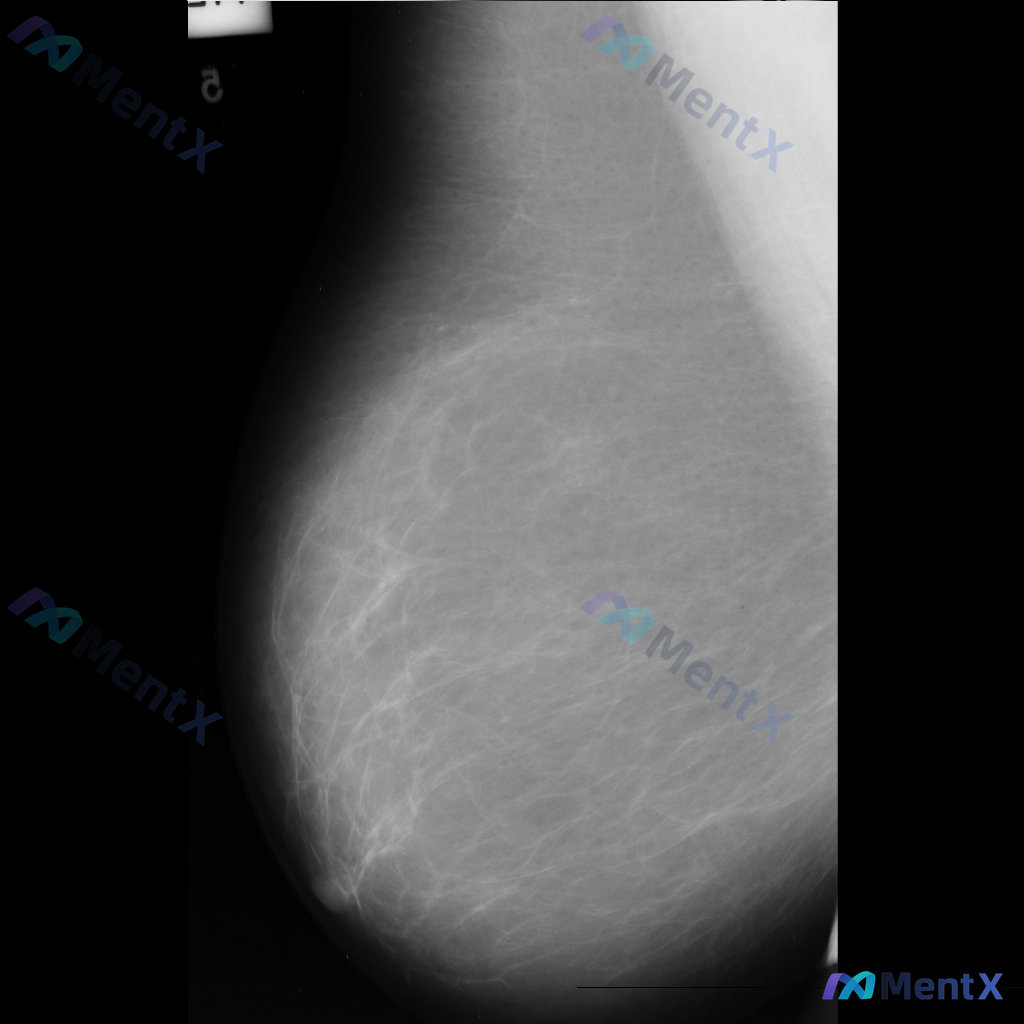

整理到一张乳腺钼靶的读片资料,想和大家一起讨论一下。 图像里能看到两处比较明确的异常: - 乳腺中下部有一个不规则、毛刺状的高密度肿块,周围还有结构扭曲的表现 - 乳腺上部还有一个类圆形的高密度肿块,形态相对规则一些 背景是不均匀致密型的乳腺组织。 单看这组图像表现,大家会优先往哪个方向考虑?